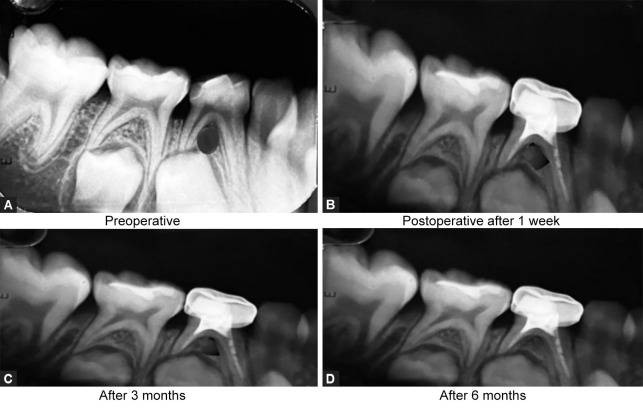

Materials and methods: The present study was conducted in 60 children of age group 4-10 years requiring multiple visit pulpectomy for their primary molars. Selected teeth were randomly divided into three groups: group I - calcium hydroxide with Ocimum sanctum, group II - calcium hydroxide with Curcuma longa, and group III - calcium hydroxide with Aloe barbadensis miller. Clinical and radiographic evaluation was done among the groups at intervals of 1 week, 3 months, and 6 months.

Results: There was no significant difference in the clinical and radiographic success rate among the groups.

Conclusion: Among the three groups, calcium hydroxide with Ocimum sanctum group showed a higher success rate and that with Aloe barbadensis miller group showed the least success rate.